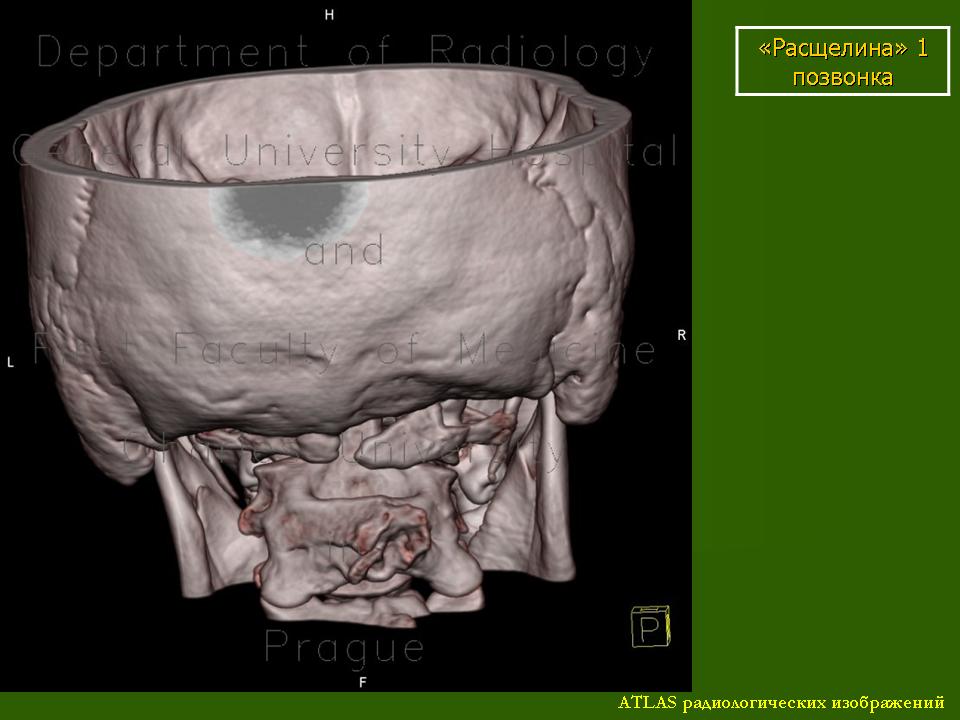

Аномалии и варианты развития позвоночника (позвонков). Ср, 19/10/2011 - 23:32 #1 Катенёв Валенти... Не на сайте Был на сайте: 7 лет 5 месяцев назад Зарегистрирован: 22.03.2008 - 22:15 Публикации: 54876 Аномалии и варианты развития позвоночника (позвонков).Приложения: Сб, 05/05/2012 - 23:43 #2 Катенёв Валенти... Не на сайте Был на сайте: 7 лет 5 месяцев назад Зарегистрирован: 22.03.2008 - 22:15 Публикации: 54876 Продолжение.Приложения: Втр, 17/07/2012 - 14:47 #3 Катенёв Валенти... Не на сайте Был на сайте: 7 лет 5 месяцев назад Зарегистрирован: 22.03.2008 - 22:15 Публикации: 54876 Продолжение.Приложения: Пт, 09/12/2016 - 19:05 #4 Катенёв Валенти... Не на сайте Был на сайте: 7 лет 5 месяцев назад Зарегистрирован: 22.03.2008 - 22:15 Публикации: 54876 Отсутствует задняя дуга С1, гипертрофия остистого отростка С2, кость выйной связки. Приложения: Сб, 10/12/2016 - 08:37 #5 Марина Сергеевна Не на сайте Был на сайте: 11 месяцев 2 недели назад Зарегистрирован: 26.04.2011 - 11:56 Публикации: 996 Видела люмбосакральную агенезию в 30 лет, кт обп+мт по поводу мкб. Могу кадров накидать. Парень инвалид-колясочник, полностью сохранен в остальном и очень позитивен. "There is no teacher, who can teach us anything new. He just can help us to remember the things we always knew" (c) Enigma. Сб, 10/12/2016 - 18:04 #6 Катенёв Валенти... Не на сайте Был на сайте: 7 лет 5 месяцев назад Зарегистрирован: 22.03.2008 - 22:15 Публикации: 54876 Марина Сергеевна wrote: Могу кадров накидать. Заранее спасибо! Втр, 13/12/2016 - 11:13 #7 Марина Сергеевна Не на сайте Был на сайте: 11 месяцев 2 недели назад Зарегистрирован: 26.04.2011 - 11:56 Публикации: 996 обещанное Приложения: "There is no teacher, who can teach us anything new. He just can help us to remember the things we always knew" (c) Enigma. Втр, 13/12/2016 - 23:10 #8 Катенёв Валенти... Не на сайте Был на сайте: 7 лет 5 месяцев назад Зарегистрирован: 22.03.2008 - 22:15 Публикации: 54876 Спасибо большое Марина Сергеевна! Чт, 16/11/2017 - 19:03 #9 Катенёв Валенти... Не на сайте Был на сайте: 7 лет 5 месяцев назад Зарегистрирован: 22.03.2008 - 22:15 Публикации: 54876 http://www.ajronline.org/doi/full/10.2214/AJR.07.7141?src=recsys Пнд, 15/01/2018 - 21:43 #10 Катенёв Валенти... Не на сайте Был на сайте: 7 лет 5 месяцев назад Зарегистрирован: 22.03.2008 - 22:15 Публикации: 54876 Аномалия Киммерли http://24radiology.ru/kostno-myshechnaya-sistema/anomaliya-kimmerle/ Пнд, 15/01/2018 - 21:52 #11 Катенёв Валенти... Не на сайте Был на сайте: 7 лет 5 месяцев назад Зарегистрирован: 22.03.2008 - 22:15 Публикации: 54876 Варианты развития позвонков. http://24radiology.ru/kostno-myshechnaya-sistema/varianty-razvitiya-pozvonkov-i-klassifikatsiya-perehodnyh-pozvonkov-po-casellvi-a-e/ Пнд, 15/01/2018 - 21:54 #12 Катенёв Валенти... Не на сайте Был на сайте: 7 лет 5 месяцев назад Зарегистрирован: 22.03.2008 - 22:15 Публикации: 54876 Вставочная кость — это оссификация передних волокон фиброзного кольца межпозвонкового диска. Вставочная кость способствует развитию в более раннем возрасте дегенеративных изменений позвоночника. http://24radiology.ru/kostno-myshechnaya-sistema/vstavochnaya-kost/ Втр, 27/02/2018 - 16:11 #13 Катенёв Валенти... Не на сайте Был на сайте: 7 лет 5 месяцев назад Зарегистрирован: 22.03.2008 - 22:15 Публикации: 54876 Шейный отдел позвоночника: нормальная анатомия, варианты и травма (у детей). http://pubs.rsna.org/doi/full/10.1148/rg.233025121 Вс, 09/09/2018 - 06:49 #14 Катенёв Валенти... Не на сайте Был на сайте: 7 лет 5 месяцев назад Зарегистрирован: 22.03.2008 - 22:15 Публикации: 54876 Врожденное недоразвитие половины позвонка https://radiopaedia.org/articles/hemivertebra Дело 1 Случай 2 Случай 3: правая боковая Т3 Случай 4 Случай 5 Вс, 09/09/2018 - 07:09 #15 Катенёв Валенти... Не на сайте Был на сайте: 7 лет 5 месяцев назад Зарегистрирован: 22.03.2008 - 22:15 Публикации: 54876 Боковая гемивертебра Случай 1: Вс, 09/09/2018 - 07:13 #16 Катенёв Валенти... Не на сайте Был на сайте: 7 лет 5 месяцев назад Зарегистрирован: 22.03.2008 - 22:15 Публикации: 54876 Block vertebra Дело 1 Случай 2 Случай 3 Случай 4: с мальформацией спинного мозга Случай 5: на уровне C2-C3 Случай 6 Случай 7 Случай 8 Вс, 09/09/2018 - 07:17 #17 Катенёв Валенти... Не на сайте Был на сайте: 7 лет 5 месяцев назад Зарегистрирован: 22.03.2008 - 22:15 Публикации: 54876 Бабочковидный позвонок Рисунок 1: фотография бабочки Дело 1 Случай 2 Случай 3 Случай 4: с кифосколизом Случай 5: поясничный S1 бабочка позвонка Случай 6 Случай 7 Вс, 09/09/2018 - 12:20 #18 Катенёв Валенти... Не на сайте Был на сайте: 7 лет 5 месяцев назад Зарегистрирован: 22.03.2008 - 22:15 Публикации: 54876 Крестец. Рисунок 1: вид спереди Рисунок 2: задний вид Случай 1: Случай 1: Случай 2. Случай 3: сакральное Вс, 09/09/2018 - 12:21 #19 Катенёв Валенти... Не на сайте Был на сайте: 7 лет 5 месяцев назад Зарегистрирован: 22.03.2008 - 22:15 Публикации: 54876 Сакральная агенезия. Дело 1 Случай 2 Случай 3: тип III у взрослого Случай 4

Аномалии и варианты развития позвоночника (позвонков).